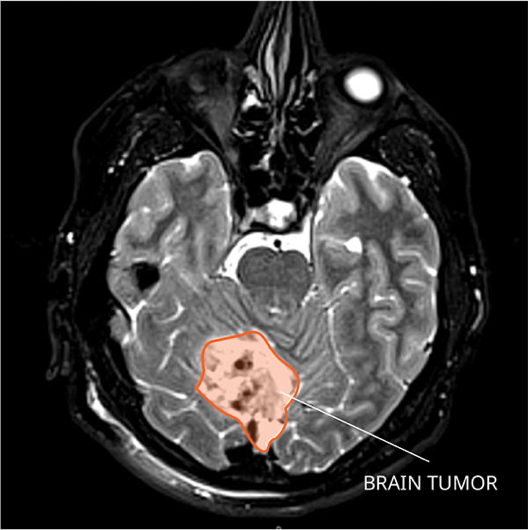

3. Glioblastoma Multiforme (GBM)

- Origin: High-grade astrocyte tumour

- Macro: Supratentorial, solid with possible cysts

- Features:

- Rapid progression, severe headache, seizures

- Personality changes, hemiparesis

- Treatment: Palliative (surgery + chemo/radiotherapy + corticosteroids)

- Prognosis: Poor (<1 year median survival)